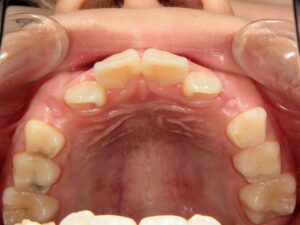

第1期治療開始時

口腔内写真

年齢

9歳 男性

主訴(患者様のお悩み)

歯のデコボコを治したい

診断

上顎前歯部叢生(上の前歯のデコボコ)

上下顎側切歯クロスバイト(部分受け口)

上顎狭窄歯列(上のあごが小さめ)

歯冠幅径大(歯が大きめ)